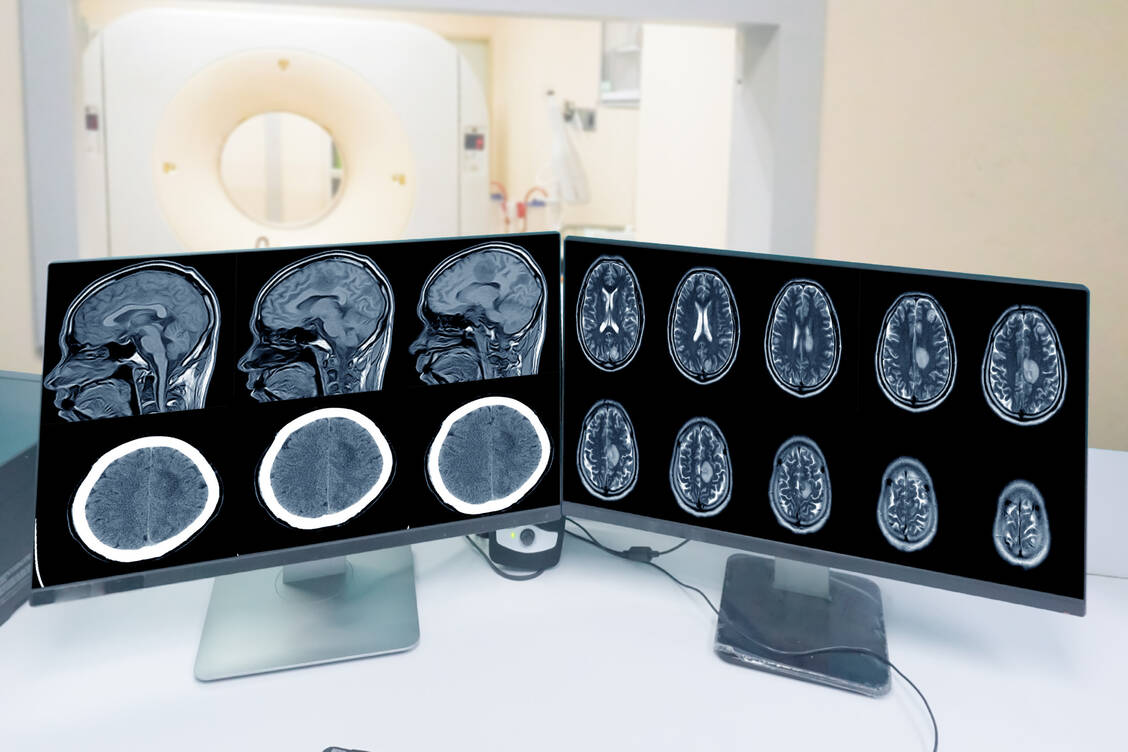

Als Nebenwirkung kann es zu Meningeomen kommen. Dies sind in der Regel gutartige Wucherungen der Hirnhäute, die das Gehirn und Rückenmark umgeben. Meningeome zählen zwar nicht zu den Krebserkrankungen, aber aufgrund ihrer Lokalisation in und rund um das Gehirn und Rückenmark können diese Tumore in seltenen Fälle schwere Probleme verursachen, begründet die Europäische Arzneimittelagentur (EMA) die neuen Maßnahmen zur Risikoreduktion.